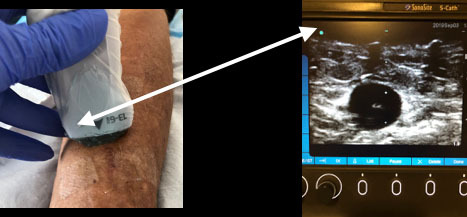

Dialysis Transducer Orientation Graphic